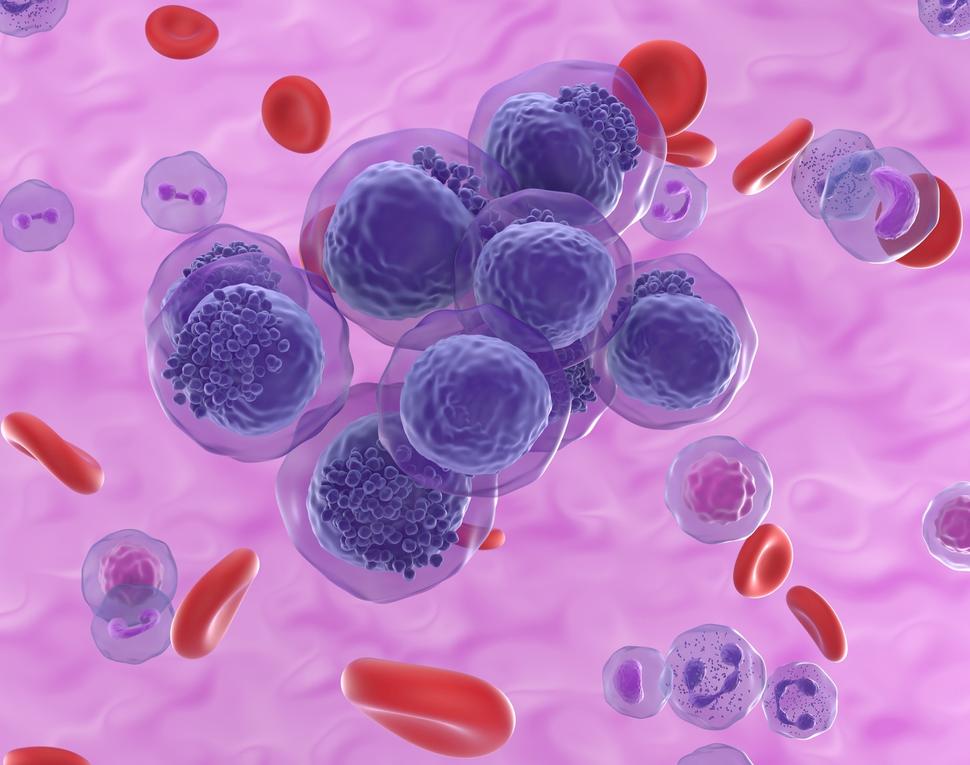

Иллюстрации из Cell Discovery: Удивительный мир науки через фотографии

Раздел: Фотоэссе